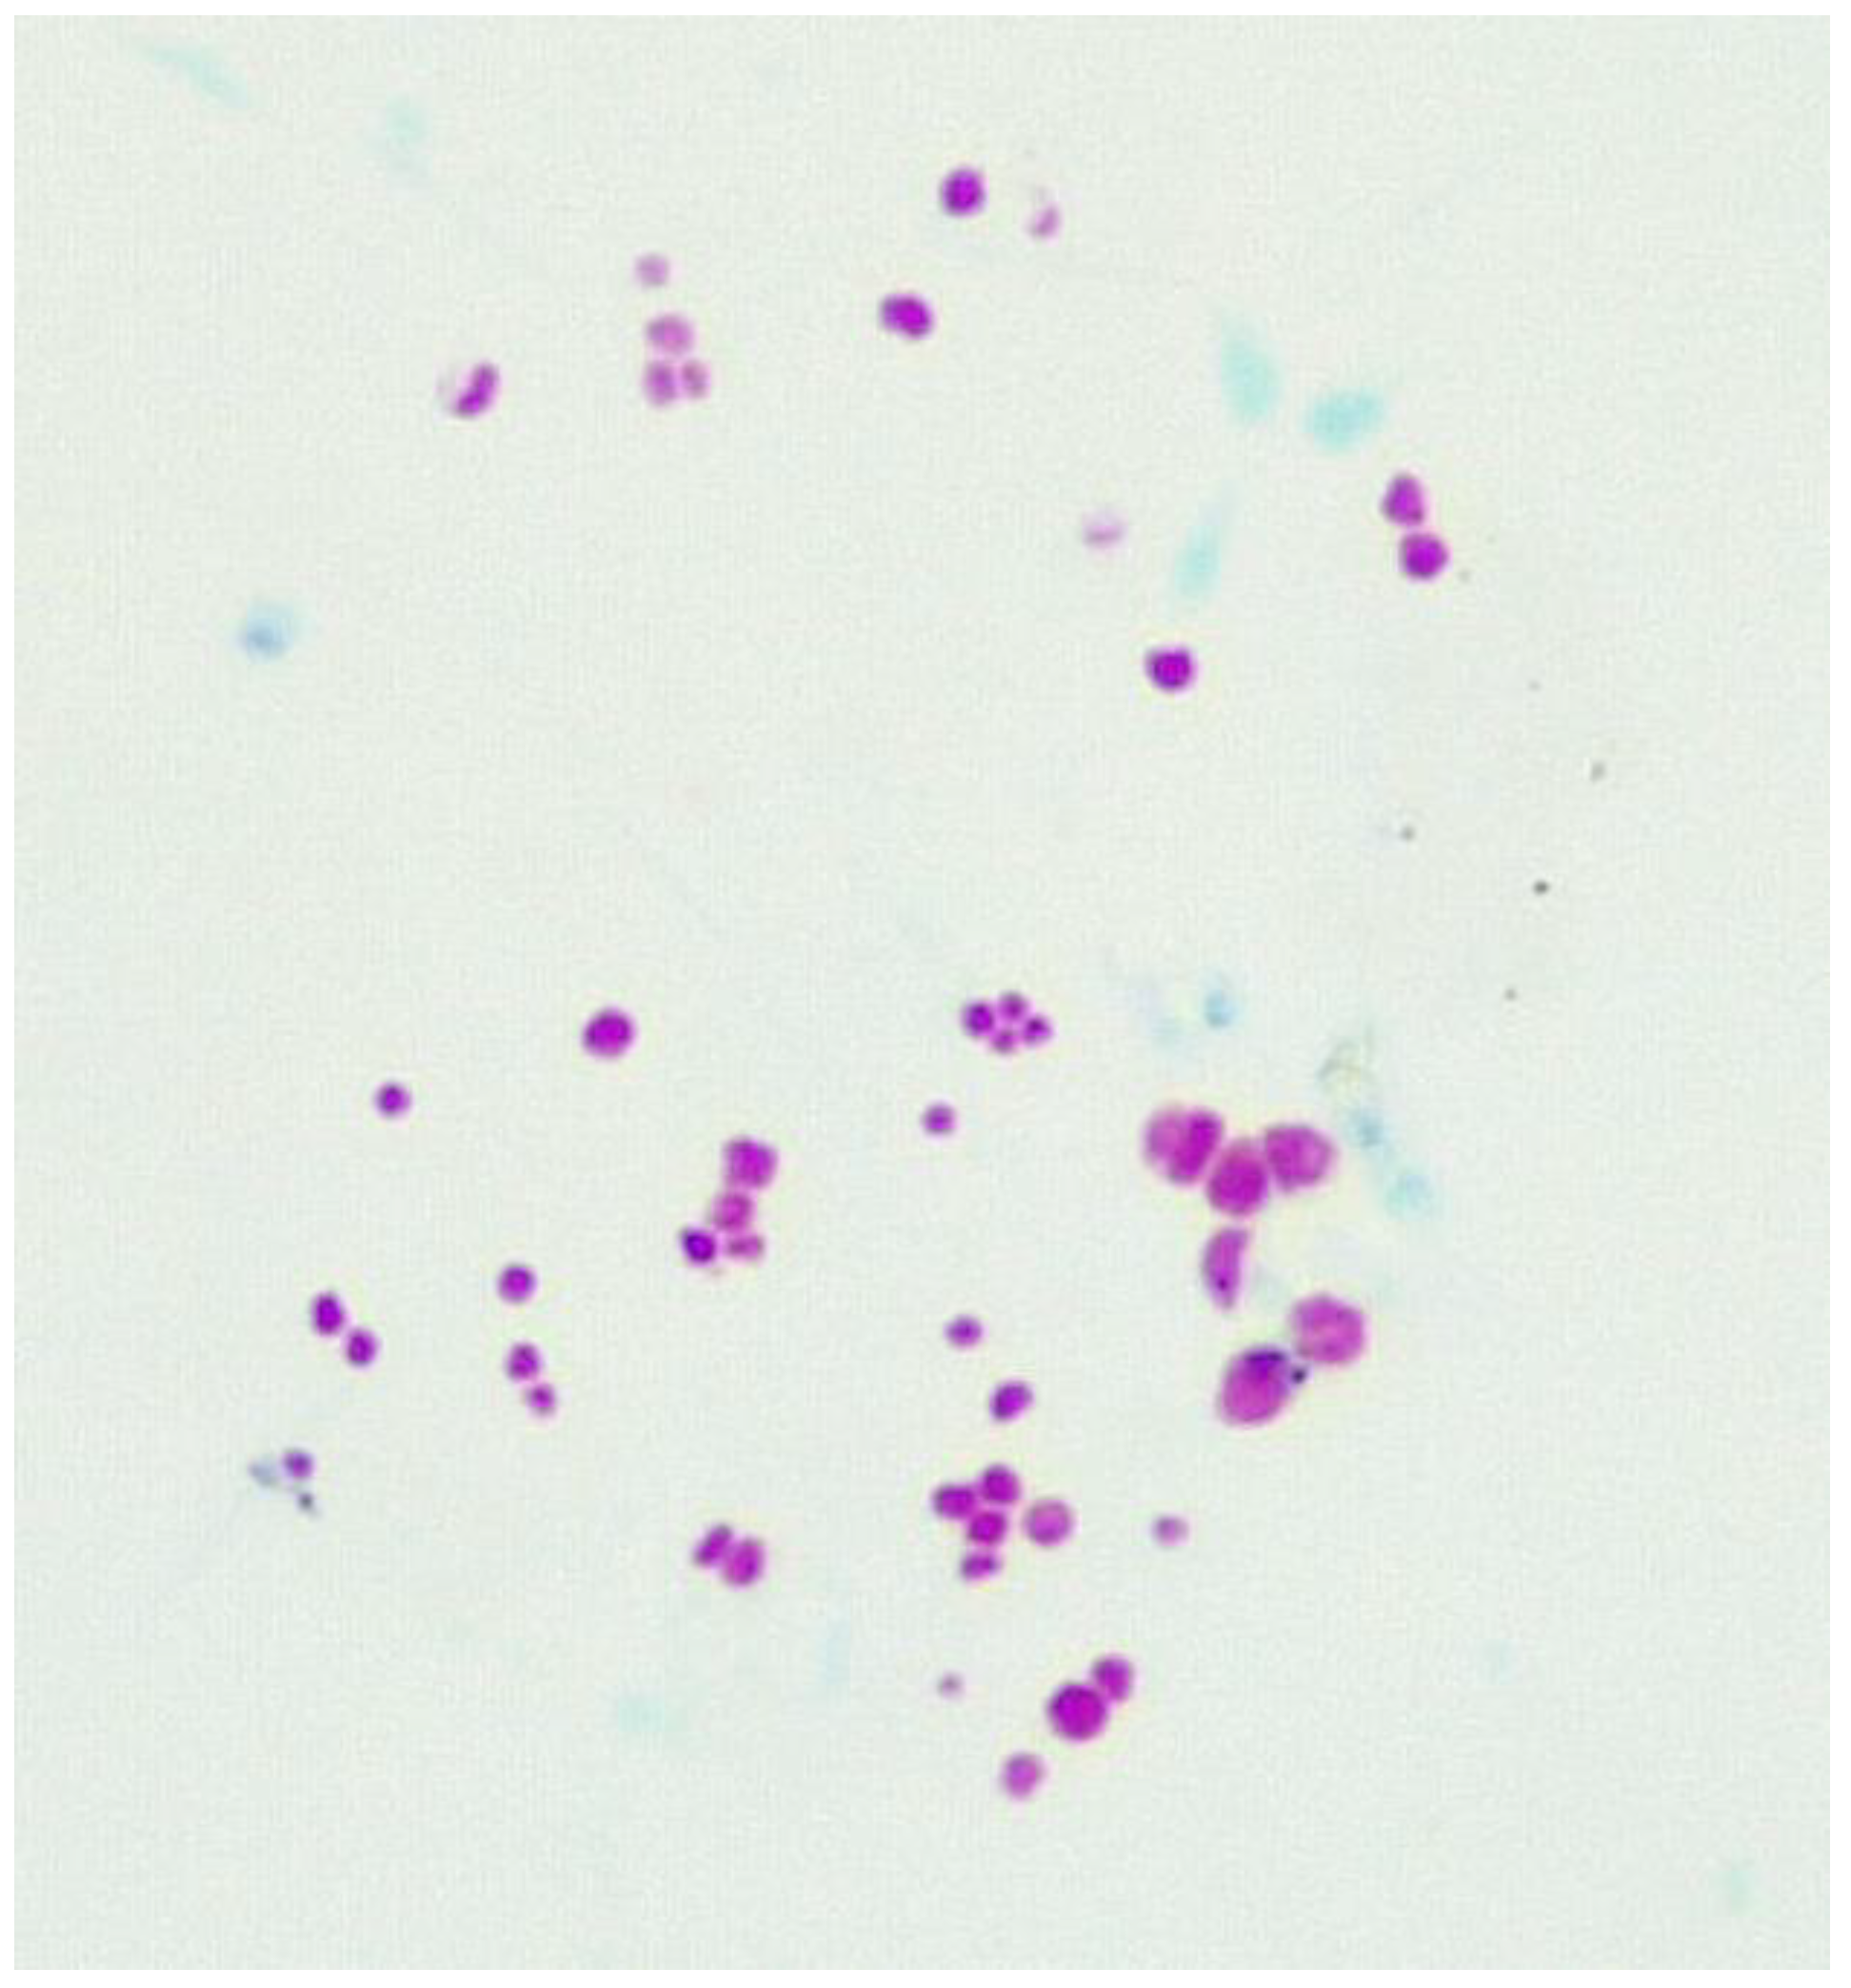

Visualising CWDM in Culture

2.1. Ziehl-Neelsen Stain for CWDM

2.2. Method for Staining

2.5. Detection of CWDM